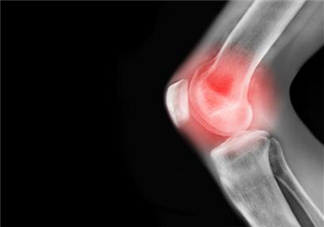

關(guān)節(jié)炎泛指發(fā)生在人體關(guān)節(jié)及其周?chē)M織的炎性疾病,可分為數(shù)十種。我國(guó)的關(guān)節(jié)炎患者有1億以上,且人數(shù)在不斷增加。臨床表現(xiàn)為關(guān)節(jié)的紅、腫、熱、痛、功能障礙及關(guān)節(jié)畸形,嚴(yán)重者導(dǎo)致關(guān)節(jié)殘疾、影響患者生活質(zhì)量。